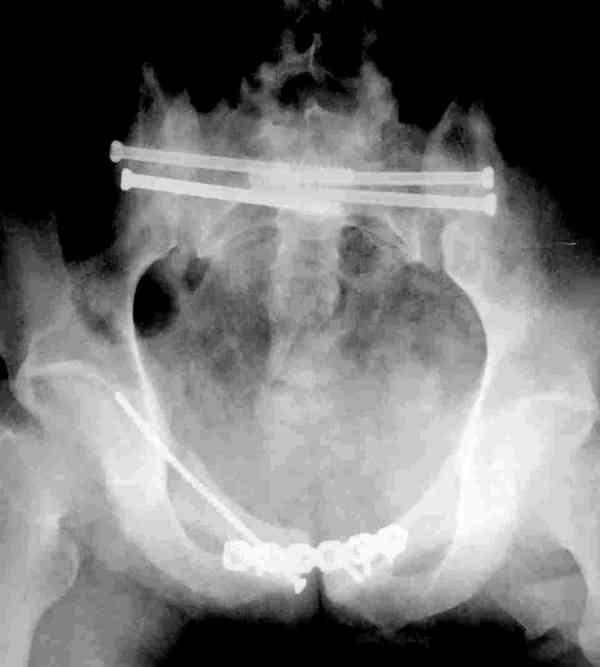

Молодой парень, без соматики. Сейчас чуть больше 2-х нед после операции, швы сняты, мочится сам. Был тяжелый, после операции дней 10 пытался выполнить лежа поперечный шпагат (успешно, так и лежал большей частью, может быть из-за обширной гематомы промежности). Репозиция не идеальная, но фиксация довольно надежная, за 2 нед ничего не "разъехалось". Сейчас пришел в ум. Когда по-вашему можно дать нагрузку и на какую ногу или на обе? Или вообще подскажете программу реабилитации.PS Заранее извиняюсь за качество снимков, до не делали (body scan), если не видно - то - полные разрывы КПС с двух сторон. после КТ сломался. Неврологии вроде бы нет.